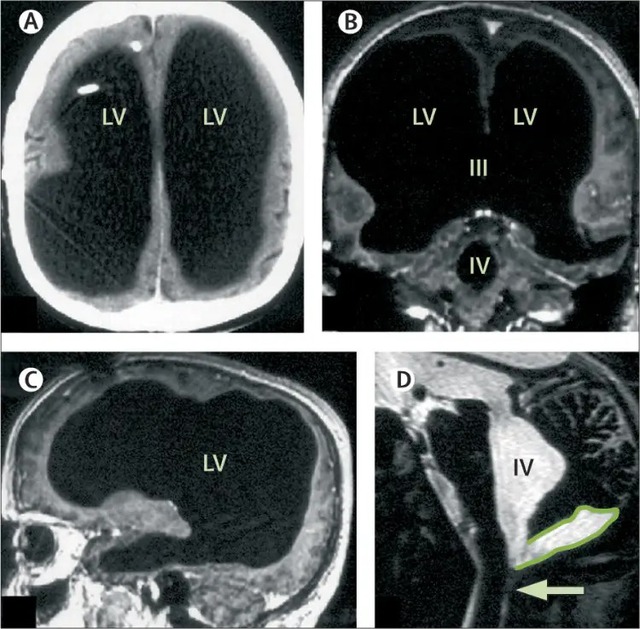

Được mô tả lần đầu tiên trên tạp chí The Lancet vào năm 2007, trường hợp của người đàn ông dường như bị mất hầu hết não đã khiến các nhà khoa học bối rối.

Những tưởng bệnh đã được khắc phục, nhưng 30 năm sau, khi ông bước sang tuổi 44, tình trạng yếu chân trái tái phát. Các bác sĩ tại Bệnh viện Marseille (Pháp) chỉ định chụp CT và MRI, và kết quả đã khiến toàn bộ ekip y khoa sửng sốt: não của ông gần như biến mất. Khoảng 75% đến 90% mô não bị tiêu hủy, thay vào đó là các khoang rỗng chứa đầy dịch não tủy.

Những hình ảnh chụp cộng hưởng từ cho thấy các thùy trán, thùy đỉnh, thùy thái dương và thùy chẩm - những khu vực đảm nhiệm tư duy, ngôn ngữ, cảm xúc và thị giác đều teo lại thành một lớp mỏng bao quanh hộp sọ. Trong điều kiện bình thường, tổn thương ở những vùng này sẽ dẫn đến suy giảm nghiêm trọng nhận thức, trí nhớ hoặc thậm chí rơi vào trạng thái sống thực vật.